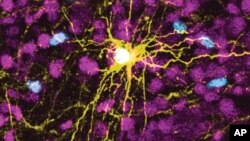

This microscope image provided by Pasca Lab/Stanford Medicine shows a human astrocyte cell, center in yellow, and human glial cells (scattered in blue) inside the brain of a rat.

Scientists have transplanted human brain cells into the brains of baby rats, where the cells grew and formed connections.

Scientists transplanted those organoids into rat pups 2 to 3 days old, a stage when brain connections are still forming. The organoids grew so that they eventually occupied a third of the hemisphere of the rat’s brain where they were implanted. Neurons from the organoids formed working connections with circuits in the brain.